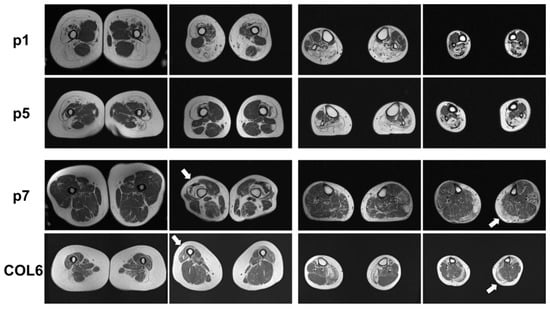

2.1. Clinical and MRI Features of Patients with BICD2-Associated Myopathy Reveal Typical Pattern of Muscle Weakness of the Legs (with Sparing of Adductor Muscles)